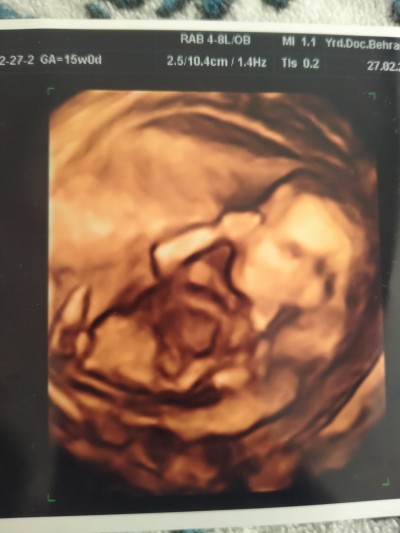

Kızlar anlayan varsa söylermisnz cinsiyettini merak ediyorum

image

Valla renkli ultrason nasıl gormedi ki doktor pozisyonuda uygun bebeğin sanki oğlan